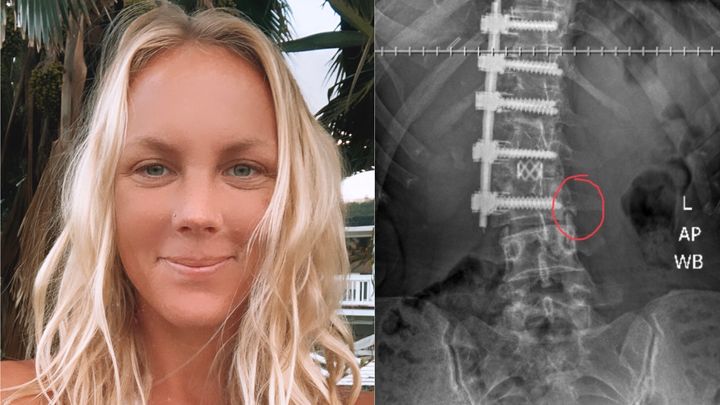

Long story short, at the age of 16 my scoliosis had gotten so severe that I had to have a spinal fusion and spent a year recovering in bed. At the time of my corrective scoliosis surgery, the doctors gave me a 10 year prognosis for when I would have to continue fusing my spine. For the past 16 years, I have been fighting like hell and doing everything humanly possible to manage my pain and prevent another surgery from being necessary. I was hoping that if I did everything "right" I would not have to face further medical intervention until much later. But here I am, needing to deal with this yet again. By now, two of my discs have degenerated to the point where they're putting pressure on my spinal cord and other nerves, which makes me absolutely miserable and causes unbearable pain.

I am 32 years old and want to live an active, healthy lifestyle. My life has already been significantly altered from my previous fusion and I hope to not have that happen again anytime soon. Fortunately, new medicine has become available that is less invasive, has a shorter recovery path, and can actually heal the discs rather than being another temporary band-aid. I'd like once again be able to perform normal daily tasks such as washing the dishes, be able to drive in my car for more than 20min, and return to work without being in agony. Even more so, as a yoga teacher and massage therapist, I have dedicated my life to being of service to others, to helping others heal and get better. With your help and the help of stem cell therapy, I hope to get back to helping others overcome their pain and hardships.